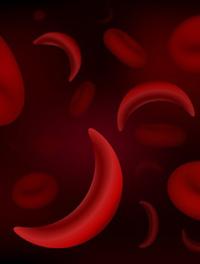

L'étude randomisée contrôlée de phase 3 HOPE a évalué l'impact du voxelotor versus placebo sur le cours évolutif de la drépanocytose [...]

Cent millions de personnes dans le monde souffrent de drépanocytose. Le mécanisme physiopathologique de la vaso-occlusion est complexe, [...]